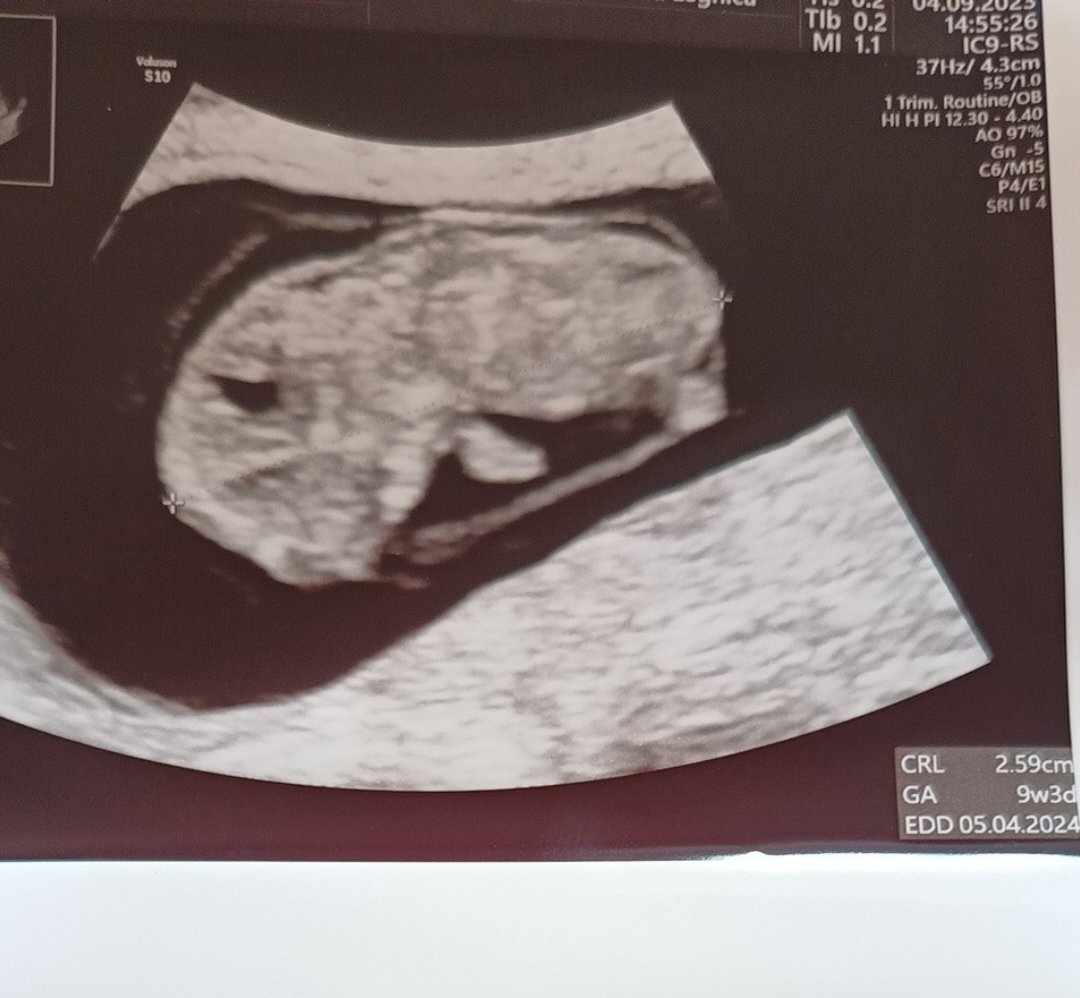

Ja dziewczyny już po wizycie. Wszystko super. Dzidziuś ma 2.59cm, serce bije, rusza się, ma dwie rączki i nóżki. Pani doktor mówiła, że między nogami jest coś więcej, ale to za wcześnie na rozpoznanie płci, bo może być przerośnięta łechtaczka u dziewczynki. Jestem taka szczęśliwa.. następna wizyta 2.10, ale to się zgrywa jakoś z terminem prenatalnych i trzeba się naszykować na wydatki.